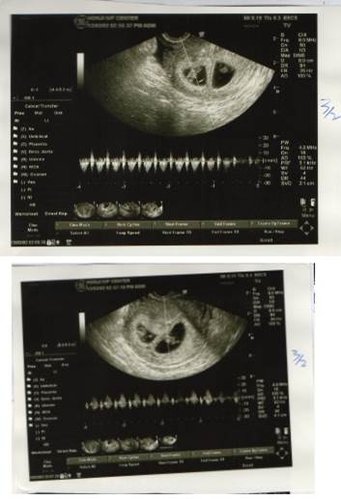

在宏孕診所第一次我只取到二顆卵,置放5天,一顆為囊胚A級,一顆為B級,玻璃冷凍後,進行第二次療程,這次取到3顆卵,2顆空包蛋,另1顆的品質似乎不如上次的2顆,因此,我決定植入上次的2顆,很順利的2顆胚胎都順利著床,也都有心跳。不過,我想此次成功原因也或許是因為我刺激的卵數少,卵子們能有較多的養分、品質較好有關,不過我想這就交給專家們去研究了!